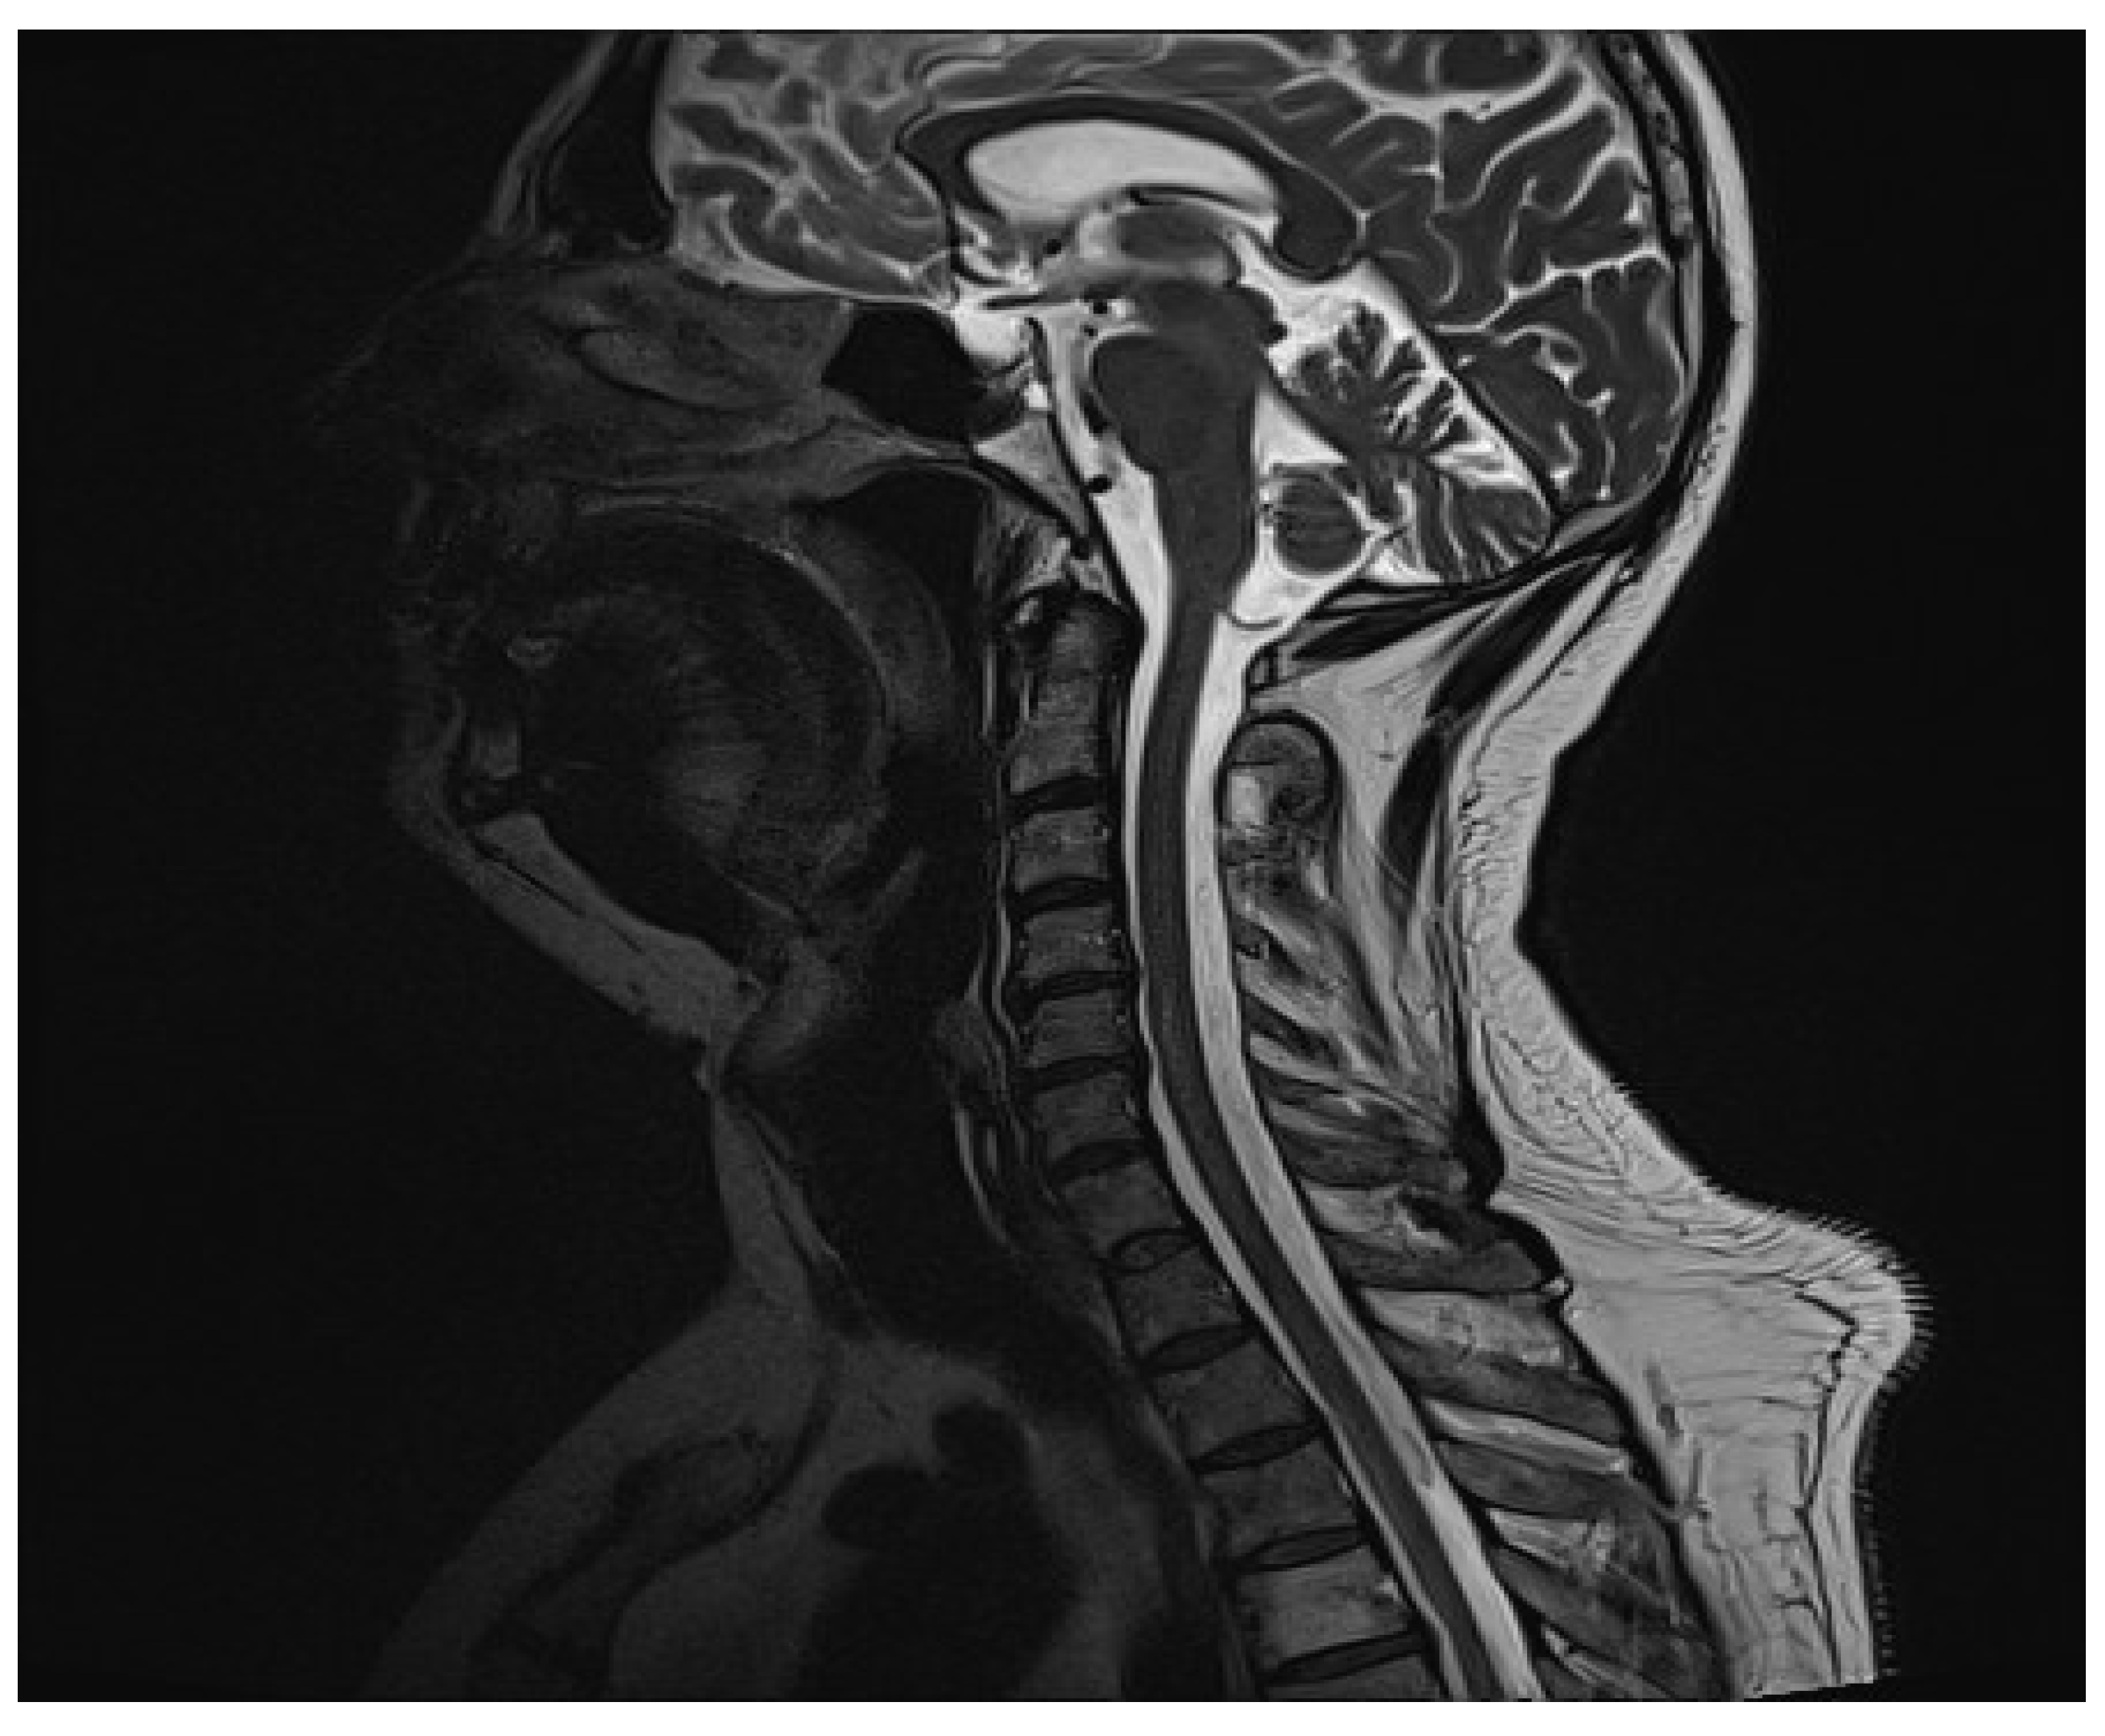

During the patient’s hospital stay, a constant weakening of the lower extremities (the right going from 5 to 3 on Lovett’s scale, the left going from 2 to 0 on Lovett’s scale) [6,7] followed by a weakening of the upper extremities (both going from 5 to 3 on Lovett’s scale) [6,7] was observed. On MR images, a radiologist found an inflammatory focus in the central part of the C5/C6 spinal cord (Figure 1). The use of contrast agents did not reveal any activity features. The patient was transferred to the neurology clinic, where more diagnostic tests were performed. The MR images of the cerebrum and the thoracic spine acquired later showed no lesions. CSF test results were typical. The biochemical CSF examination revealed elevated total protein (0.91 g/L) and elevated albumin (656.7 mg/L) levels. Intradural type 4 oligoclonal band synthesis, as defined in the Charcot Foundation standards, was not observed. The CSF culture test and PCR test for the presence of pathogens in CSF were negative. The fluid culture test was negative. The aquaporin-4 antibody test was negative. The result of the anti-MOG antibody test performed on 13 October 2022 was slightly elevated (1:10). The result of another trial, conducted on 18 October 2022, was <1:10, which is described as unfavorable. Then, connective tissue disorders were ruled out, and the patient was referred for a rheumatological consultation.

Figure 1. The MRI of the cervical spine on the T2-weighted short tau inversion recovery scan showed a hyperintense lesion on C5–C6.